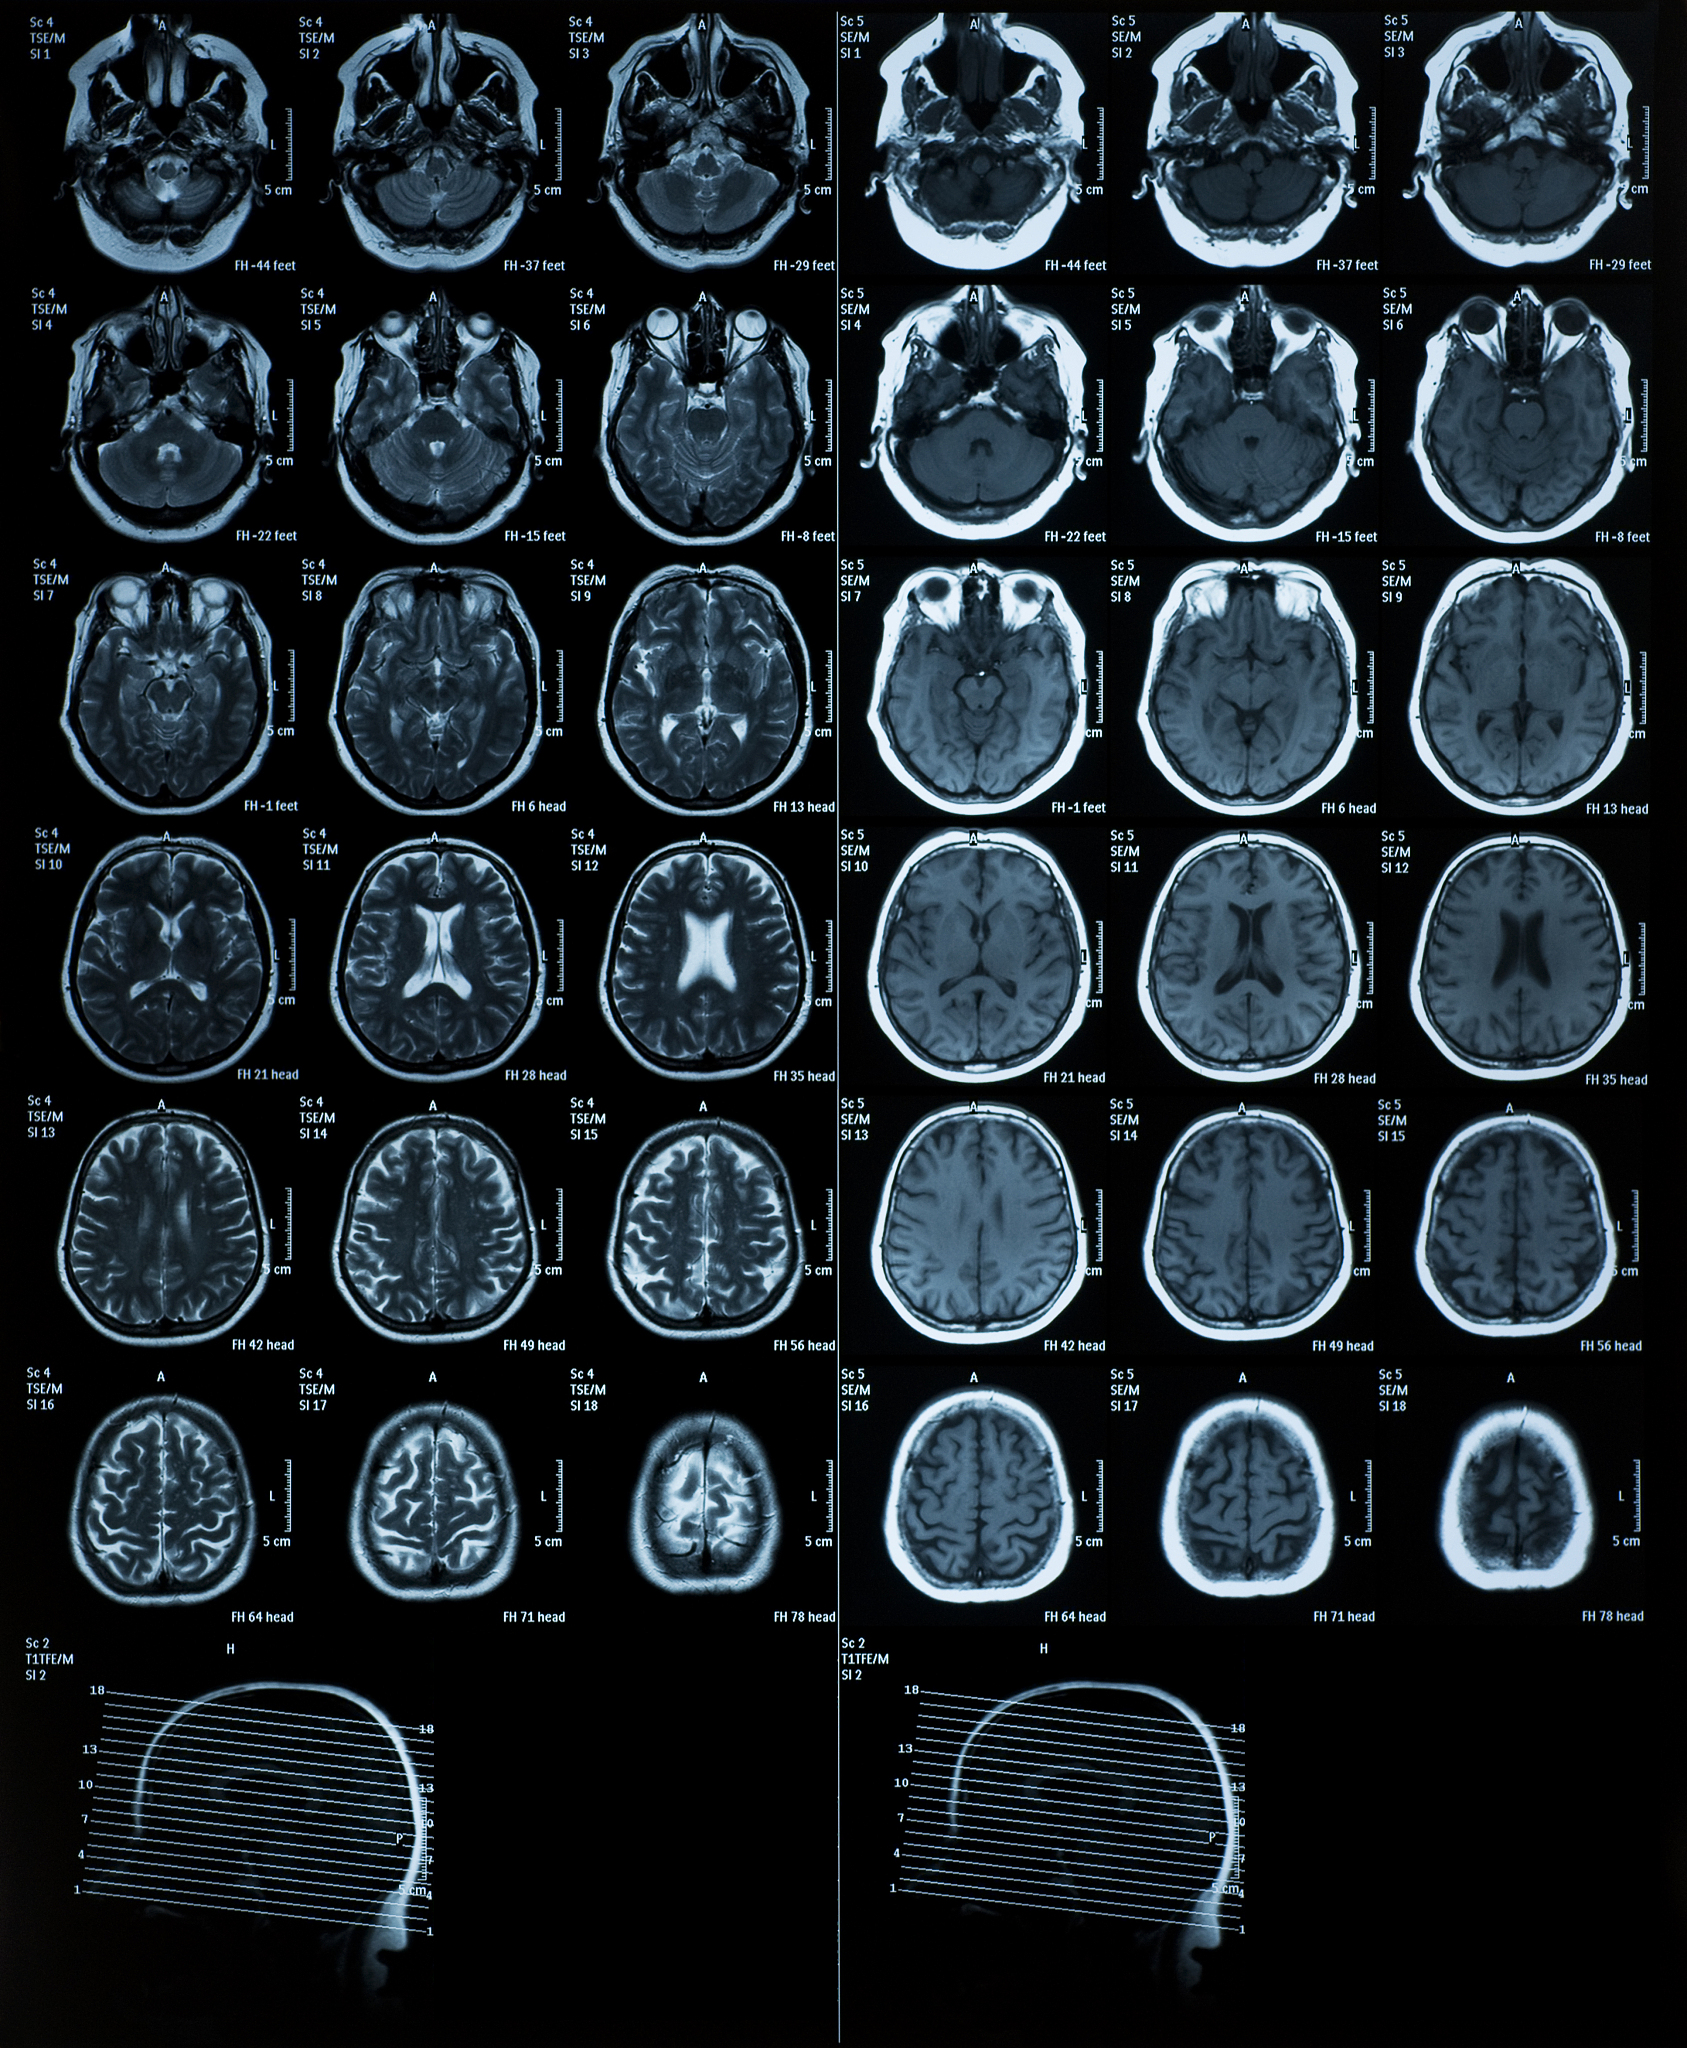

患者近期接受了右额颞部位手术,术后行MRI检查评估恢复情况。影像结果显示:

1. 术区改变:

• 右额颞顶部骨质呈术后改变,提示手术区域骨组织愈合情况良好。

• 骨瓣下右额颞可见片状T1WI低信号和T2WI高信号,周围可见少量FLAIR略高信号,DWI示术区弥散未受限。这可能与术后组织水肿、炎症或胶质增生有关,需结合临床症状和病史进行判断。

• 增强扫描后术区脑膜可见线样轻度强化,提示术后脑膜可能存在轻度炎症反应,需密切随访观察。

2. 其他发现:

• 双额顶叶皮层下可见斑点状T1WI等T2WI高信号,FLAIR序列示为略高信号,边界不清。这可能与多种因素有关,例如小血管病变、胶质增生等,需结合临床进一步明确诊断。

• 蝶鞍不大,垂体形态及信号未见明显异常,提示蝶鞍及垂体目前未受明显影响。

• 右侧脑室颞角扩大变形,局部脑沟裂欠规则,可能与先前的病变或手术影响有关。

• 中线结构居中,扫描所示鼻窦及双侧眼球未见明显异常,提示颅内结构总体保持稳定。

总结: MRI结果显示右额颞部位术后改变符合预期,但仍需结合临床信息综合判断。建议患者定期复查,密切关注术后恢复情况,以及其他影像学发现的进展。如有任何疑问,请咨询专业医生。

右额颞术后MRI影像分析:骨质改变、脑膜强化及其他发现